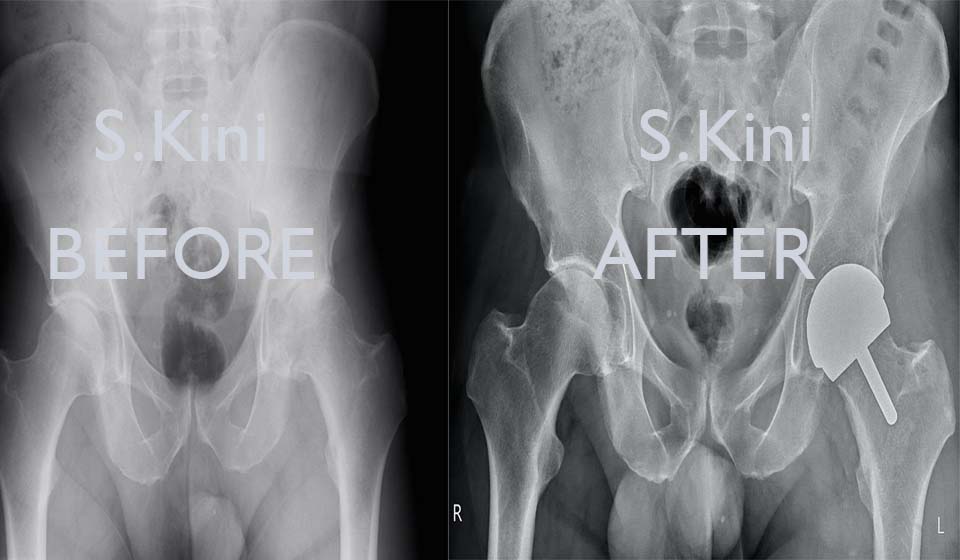

Hip resurfacing is a type of hip replacement which replaces the two surfaces of the hip joint.

The procedure is very bone conserving as the head of the femur is retained. Instead of removing the head completely, it is shaped to accept an anatomically sized metal sphere.

The surface of the acetabulum (the socket) is replaced with a metal implant, which is fitted directly into the bone.